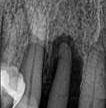

Read MorePerioscopy: A Non-Invasive Option for Moderate to Advanced Periodontitis

I am privileged to work with some talented individuals on the team. This case by advanced hygienist Laurie Ujfalussy features a moderate to advanced localised periodontitis situation in a 50 […]